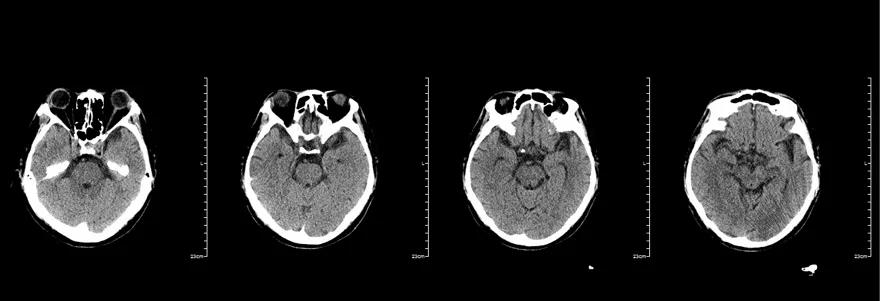

入院时头颅CT(图2):少量蛛网膜下腔出血。

图2. 入院时头颅CT